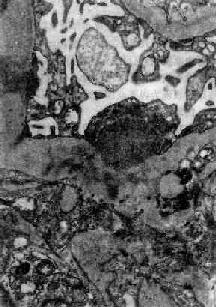

图12-7 弥漫性毛细血管内增生性肾小球肾炎 肾小球内细胞数量增多,系膜细胞和内皮细胞增生并有少量中性白细胞浸润,毛血管腔狭窄 上皮细胞一般无明显增生,少数严重的病例肾小球的壁层和脏层上皮细胞可增生,形成新月体。这种病变容易引起肾小球纤维化。如数量少,对功能影响不大。如病变广泛,可发展为新月体性肾炎。 在电子显微镜下可见肾小球系膜细胞和内皮细胞增生肿胀。基底膜和脏层上皮细胞间有致密物质沉积。这些沉积物大小不等,有的很大,在基底膜表面呈驼峰状或小丘状(图12-8,图12-9)。沉积物表面的上皮细胞足突多消失。基底膜变化不明显有时边缘稍不规则。沉积物一般在发病后几天就可出现,在4~6周内消失。有时基底膜内侧内皮细胞下和系膜内也可见小型沉积物。